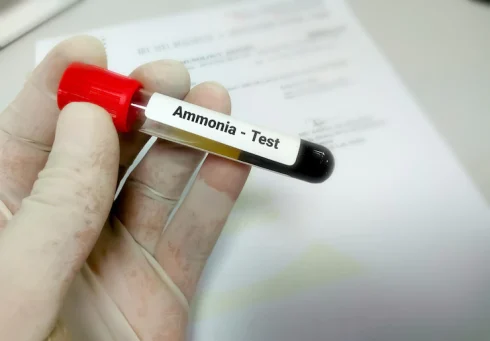

آزمایش آمونیاک خون چیست؟ تفسیر نتایج آزمایش آمونیاک

آزمایش آمونیاک خون چیست؟ آزمایش آمونیاک خون یک آزمایش خون ساده است که به پزشک[بیشتر بخوانید]